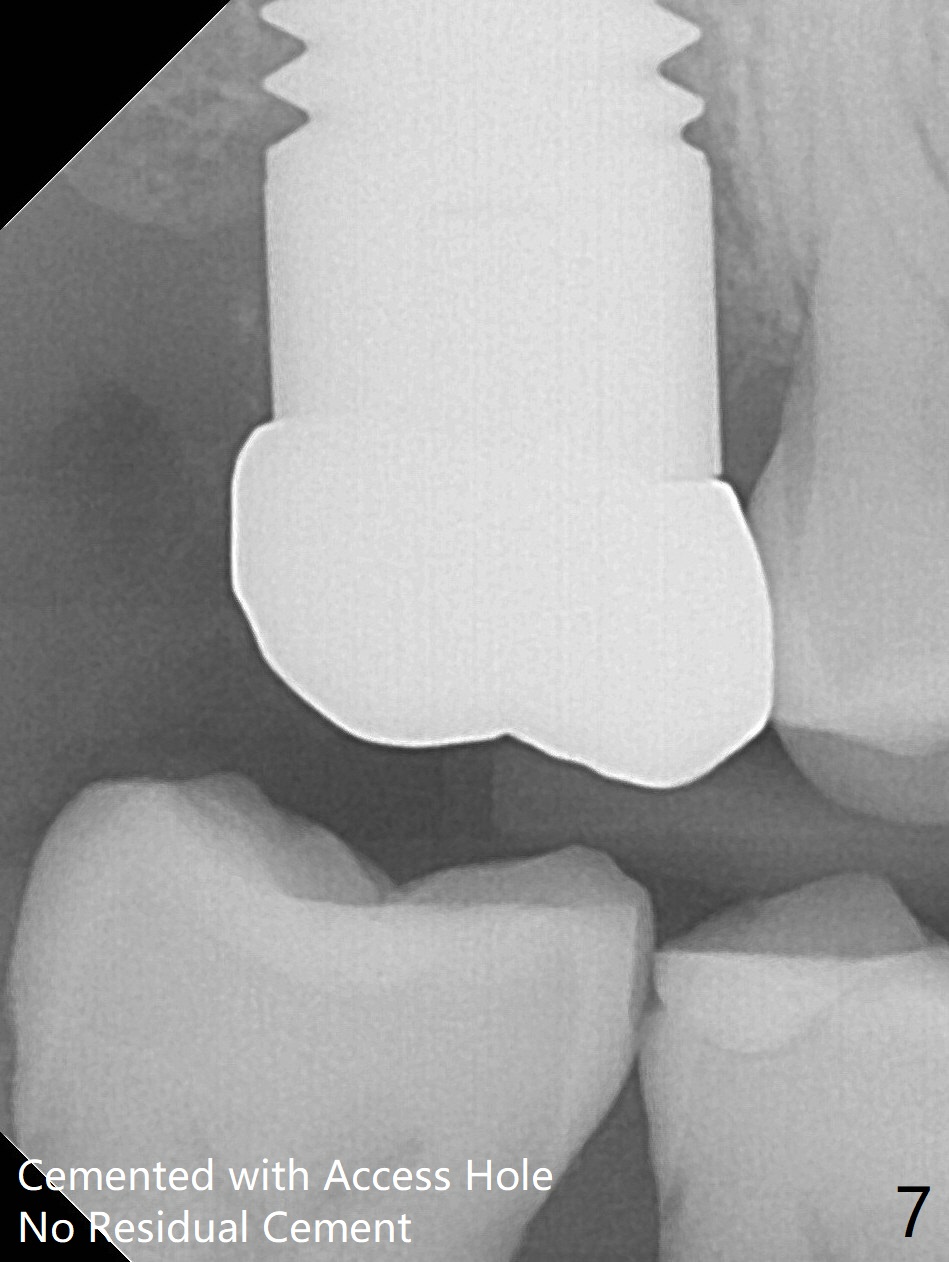

Preop exam shows that the tooth #2 has split into the buccal (Fig.1 B) and palatal (P) halves. When the tooth is extracted (Fig.2), there is a large piece of granulation tissue between these halves. The socket is large with sinus floor having pointed perforation. The latter is enlarged with rounded tapered Tatum osteotomy 2-4 mm, followed by tapered and then rounded taps. A 6.8x14 mm rounded tap has barely enough stability (Fig.3). Following placement of 2 PRF plug and 2 PRF membranes and allograft/Osteogen, a 8x17 mm cylindrical implant is placed with 60 Ncm (implant machine reading), however the implant is unstable (Fig.4). More graft is placed around the implant. With placement of 6x3 mm abutment, an immediate provisional is fabricated to close the socket. There is nasal discharge for a few days postop. PAs taken nearly 6 months postop show no bone loss (Fig.5,6). The definitive crown is cemented with access hole; there is no residual cement (Fig.7 (9 months postop)). The crown is loose 1 month post cementation (last March, Fig.8 with periimplant space (*)). The unipost was not cemented due to gag reflex. He refuses treatment immediately because of the allergy season. When he returns, spray a topical to his throat. Following crown removal, implant is found to have mobility. Panoramic X-ray (Fig.9) and CT (Fig.10,11) show fibrointegration (space) and implant intrusion into the sinus (S) without bone formation. After implant removal, the sinus floor and membrane are found to have been perforated. Osteogen plug is placed, followed by Vanilla/Osteogen (Fig.12 *) and Osteogen plug. It appears that an immediate implant is contraindicated when there is severe infection (Fig.2) with sinus floor perforation. In this case, the bone density at the upper 2nd molar is low (Fig.10 distopalatal view of 3-D image). Bone expansion and condensation is needed for implantation. Progressive loading is also necessity prior to impression.